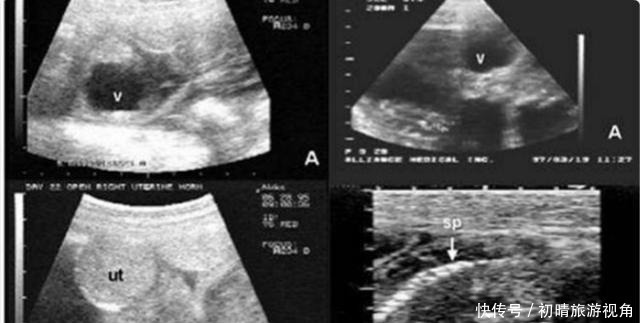

这对英国的夫妻,在结婚多年后才拥有了自己的孩子,妻子在怀孕的时候就非常的喜悦。他们如期进行孕检,却没想到在怀孕三个月的时候去医院检查被医生告知胎儿的脊柱存在断裂的情况,希望这对夫妻放弃这个孩子,可是这对夫妻并没有放弃。在怀孕8个月的时候去产检,医生告诉他们,胎儿目前这个情况,即使是出生,孩子大脑发育也不完全,抚养困难很大。

胎儿脊柱裂有什么影响?胎儿脊柱裂是一种先天性的骨骼疾病,可以在孕18-22周检查出来。其包括两种情况,一种是隐性的,另一种是显性的,显性脊柱裂会影响到宝宝以后的下肢活动,大小便失禁,甚至会影响智商,隐性脊柱裂一般不会有太大影响。如果查出胎儿是显性的脊柱裂,一般情况下医生都会建议终止妊娠。